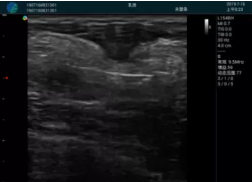

甲狀腺囊性結(jié)節(jié),囊壁鈣化,透聲好

甲狀腺囊性占位